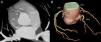

A 74-year-old man, with a history of heavy smoking, presented with unstable angina (Figure 1). Dobutamine stress echocardiography showed ischemia in the right coronary artery territory. Coronary angiography revealed no obstructive epicardial disease in the left dominant circulation (Figure 2A); the right coronary artery (RCA) was a small caliber and tortuous vessel, with only minor atheroma. However, an abnormal vessel arising from the proximal RCA was noted (Figure 2B and C), confirmed as a fistulous connection to the left atrium by multislice computed tomography, which also excluded other vascular anomalies (Figure 3). This was deemed to be causing a coronary steal phenomenon. Exercise myocardial perfusion imaging under anti-ischemic therapy excluded residual ischemia and the patient was successfully conservatively managed (Figure 4).

Multislice computed tomography. (A): 2D multiplanar reformatted image revealing a fistulous connection (arrows) between the proximal right coronary artery (RCA) and the left atrium (LA). (B): 3D volume-rendered image showing the fistula (arrows) arising from the proximal right coronary artery with a retro-aortic course. RA: right atrium; RVOT: right ventricular outflow tract.